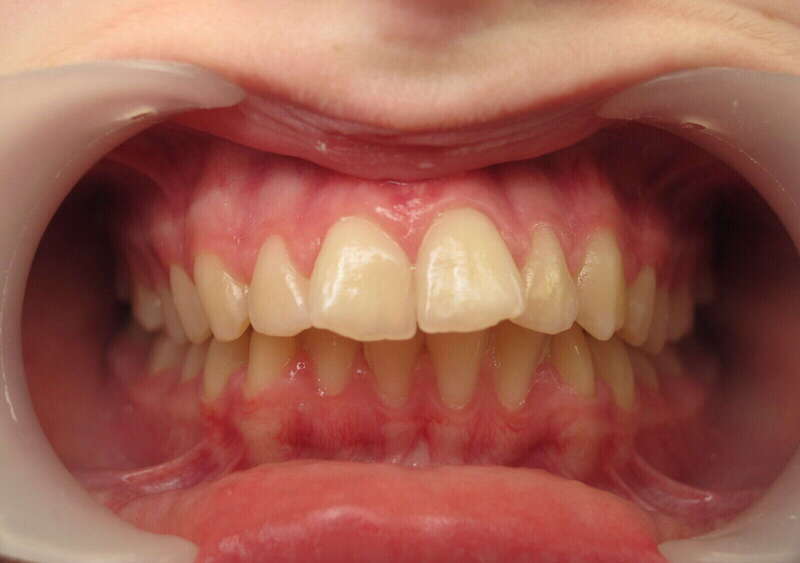

Cas n°7 traité par appareil multi-attaches - adolescent

Ce cas illustre la réussite d'un traitement orthodontico-chirurgical complexe chez un patient adolescent. La problématique initiale associait un encombrement dentaire sévère, une Classe II squelettique (mandibule en retrait) et une supraclusion marquée, verrouillant l'articulation.

Le traitement a été conduit avec des brackets autoligaturants, une technologie de pointe permettant un alignement fluide et une préparation des arcades optimale par une gestion précise des forces de friction. Cette phase orthodontique a permis de lever les compensations dentaires pour préparer l'étape chirurgicale de repositionnement mandibulaire.

• Harmonie faciale : L’avancée chirurgicale a radicalement équilibré le profil.

• Occlusion fonctionnelle : Obtention d'un engrènement de Classe I stable et correction totale de la supraclusion.

• Esthétique : Un sourire élargi et parfaitement aligné.

Bénéfices santé : Au-delà de l'esthétique, ce traitement protège les articulations temporo-mandibulaires (ATM) et prévient l'usure dentaire prématurée. Chez l'adolescent, cette transformation fonctionnelle et morphologique est essentielle pour la santé respiratoire, la mastication et le renforcement de l'estime de soi.